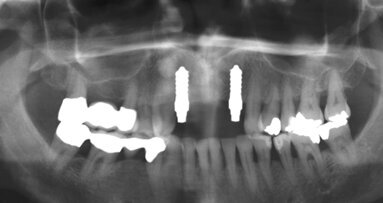

LEIPZIG - Im Live-Tutorial am 22. November 2019 um 14 Uhr demonstriert Dr. Ulf Meisel anhand eines Fallbeispiels den komplett metallfreien Workflow einer verzögerten Sofortimplantation mit Sofortversorgung im ästhetischen Bereich.

Unter Verwendung eines zweiteilig verschraubten Keramikimplantats (Bone Level Straumann Snow Implantat) geht er detailliert auf alle Behandlungsschritte – von der Implantatbettaufbereitung bis hin zur Verschraubung der metallfreien Suprakonstruktion – ein.

Im Laufe der letzten Jahre haben Keramikimplantate zunehmend an Bedeutung gewonnen. Besonders in Bezug auf die ganzheitliche Zahnmedizin sind diese als Alternative zu den etablierten Titanimplantaten nicht mehr wegzudenken. Sie vereinen Biokompatibilität, Biomechanik und Ästhetik in einem hohen Maß. Nach erfolgreicher Etablierung einer osseointegrationsfähigen Keramikoberfläche war die Herausforderung, eine komplett metallfreie Implantologie zu etablieren.